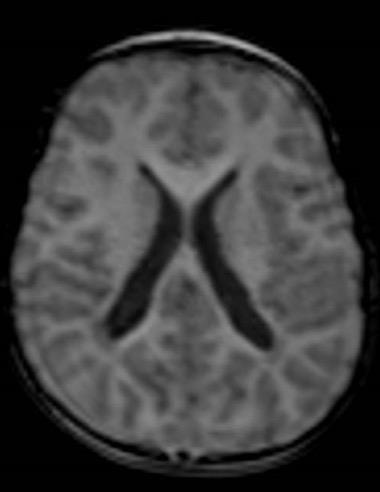

- Imaging: Periventricular leukomalacia, thinning of the corpus callosum

- Diagnosis: Spastic diplegia secondary to cerebral palsy RM 1/10/2019

01/22 NHC Admission for Preoperative Assessment

Brain and spinal cord MRI under general anesthesia